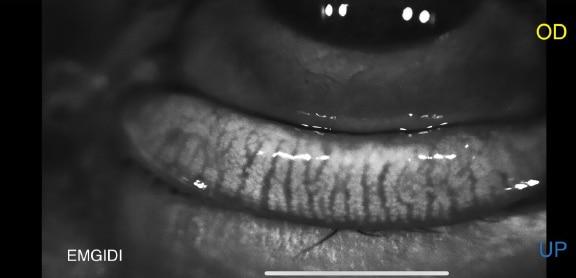

Stade 3

Plus de 66% des glandes atrophiées